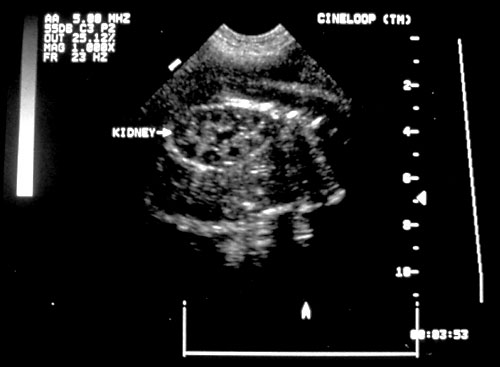

- Kidneys — look for renal pyelectasis (renal pelves > 4mm less than 20 weeks or > 1 cm after 28 weeks)

Normal appearing kidneys in transverse orientation (left). Normal sagittal view of kidney (right).